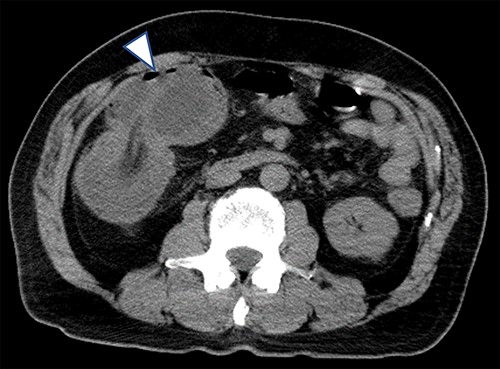

A 63-year-old male who had fever and dyspnea visited a medical institution. Both antigen and polymerase chain reaction (PCR) tests for SARS-CoV-2 were positive and he was hospitalized for treatment. Nine days after admission, he was transferred to our hospital due to deteriorating respiratory condition. After admission to our hospital, ventilator management and steroid administration were performed. After 3 days, his respiratory condition improved and he was able to withdraw from the ventilator. Computed tomography (CT) taken for observation of lung disease coincidentally showed cystic lesions in the right abdomen (Fig. 1). He had no abdominal symptoms at this time. The patient was discharged on the 18th day of hospitalization. He had diarrhea from the 15th day after discharge and abdominal pain from the next day. He consulted his family doctor on the 17th day because the abdominal pain persisted. CT examination revealed enlargement of cystic lesion and intussusception of the right colon (Fig. 2). The patient was transferred to our hospital as an emergency case. Physical findings showed fever with a body temperature of 38°C and tenderness in the right lower abdomen. Blood test showed an inflammatory reaction with a white blood cell count of 13 000/μl and C-reactive protein of 2 mg/dl. The SARS-CoV-2 PCR testing was negative. We performed emergency surgery on the same day.

Plain CT taken when the patient was transferred to our hospital for abdominal pain; the cystic lesion had increased in size (arrowhead) and showed intussusception.